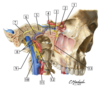

59

#1

#1 - parotid gland

60

#2

#2 - main trunk of facial nerve emerging from stylomastoid foramen

61

#3

#3 - sternocleidomastoid muscle

62

#4

#4 - external jugular vein

63

#5

#5 - temporal branche of facial nerve

64

#6

#6 - parotid duct

65

#7

#7 - masseter muscle

65

#8

#8 - facial artery and vein

65

#9

#9 - cervical branch of facial nerve

66

#1

#1 - sphenopalatine artery

67

#2

#2 - posterior superior alveolar artery

68

#3

#3 - descending palatine artery in pterygopalatine fossa

69

#4

#4 - inferior alveolar artery

69

#6

#6 - deep temporal arteries and nerves

70

#5

#5 - middle meningeal artery

71

#1

#1 - lateral pterygoid muscle

72

#1

#1 - medial pterygoid muscle

73

#1

#1 - ciliary ganglion

74

#2

#2 - short ciliary nerves

75

#3

#3 - inferior division of oculomotor nerve

76

#4

#4 - pterygopalatine ganglion

77

#5

#5 - abducent nerve (CN VI)

78

#6

#6 - ophthalmic nerve (CN V1)

79

#7

#7 - oculomotor nerve (CN III)

80

#8

#8 - trochlear nerve (CN IV)

81

#1

#1 - trochlear nerve (IV)

82

#2

#2 - opthalmic nerve (V1)

83

#3

#3 - optic nerve (II)

84

#4

#4 - oculomotor nerve (III)

85

#5

#5 - abducent nerve (VI)

86

#6

#6 - trigeminal (semilunar) ganglion

87

#7

#7 - frontal nerve

88

#8

#8 - lacrimal nerve

89

#9

#9 - supra-orbital nerve